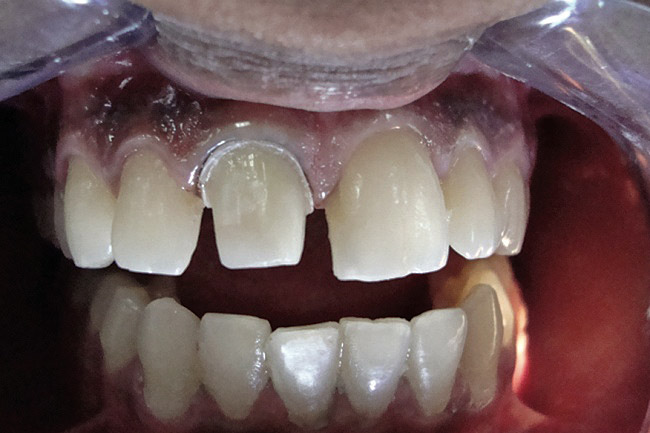

Figure 2  Caries extending cervically on upper right incisors.

Figure 2

Figure 3  Placement of rubber dam with application of cervical clamp on central incisor for extra retraction.

Figure 3